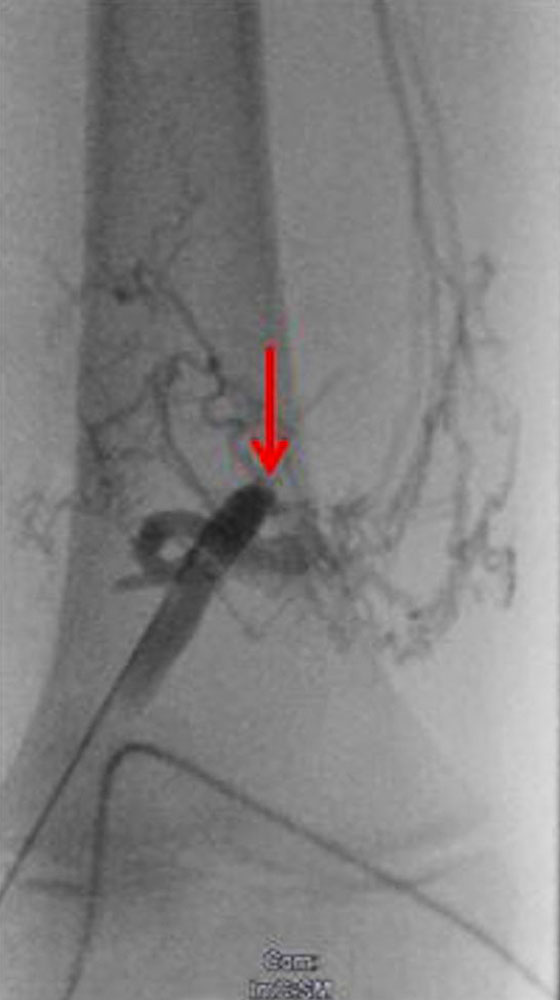

Bei einigen Patientinnen mit bisher unbehandelten oder nicht suffizient behandelten venösen Malformationen, bei denen eine Verbindung ins tiefe Leitvenensystem vorliegt („Kommunikationsvene“ oder Marginalvene) mit entsprechend erhöhter Gefahr einer Thrombose oder Thrombembolie, kann die Gefahr dieser Komplikation während der Schwangerschaft erhöht sein. Eine entsprechende Therapie vor der Schwangerschaft mit interventionellem oder operativem Verschluss dieser Kommunikationsvenen kann dieses Risiko erheblich vermindern oder ausschließen. Bei einzelnen Patientinnen kann zudem in Abwägung des individuellen Risiko-Nutzen-Verhältnisses während der Schwangerschaft eine längerdauernde Antikoagulation mit Heparin sinnvoll und notwendig sein. Daten liegen hier vor bei Patientinnen mit Klippel-Trénaunay-Syndrom (KTS), die allerdings keine ganz einheitlichen Ergebnisse zeigten. Einerseits bestand kein Unterschied in der Komplikationshäufigkeit zwischen schwangeren und nicht schwangeren Frauen mit Klippel-Trénaunay-Syndrom, dennoch war das Komplikationsrisiko im Vergleich zu Normalschwangeren erhöht, auch trat eine doppelt so hohe Rate an postpartalen Blutungen auf. In einer weiteren Studie, die KTS-Patientinnen mit nicht erkrankten Schwangeren verglich berichteten 43 % der KTS-Patientinnen über mehr Symptome während Schwangerschaft.